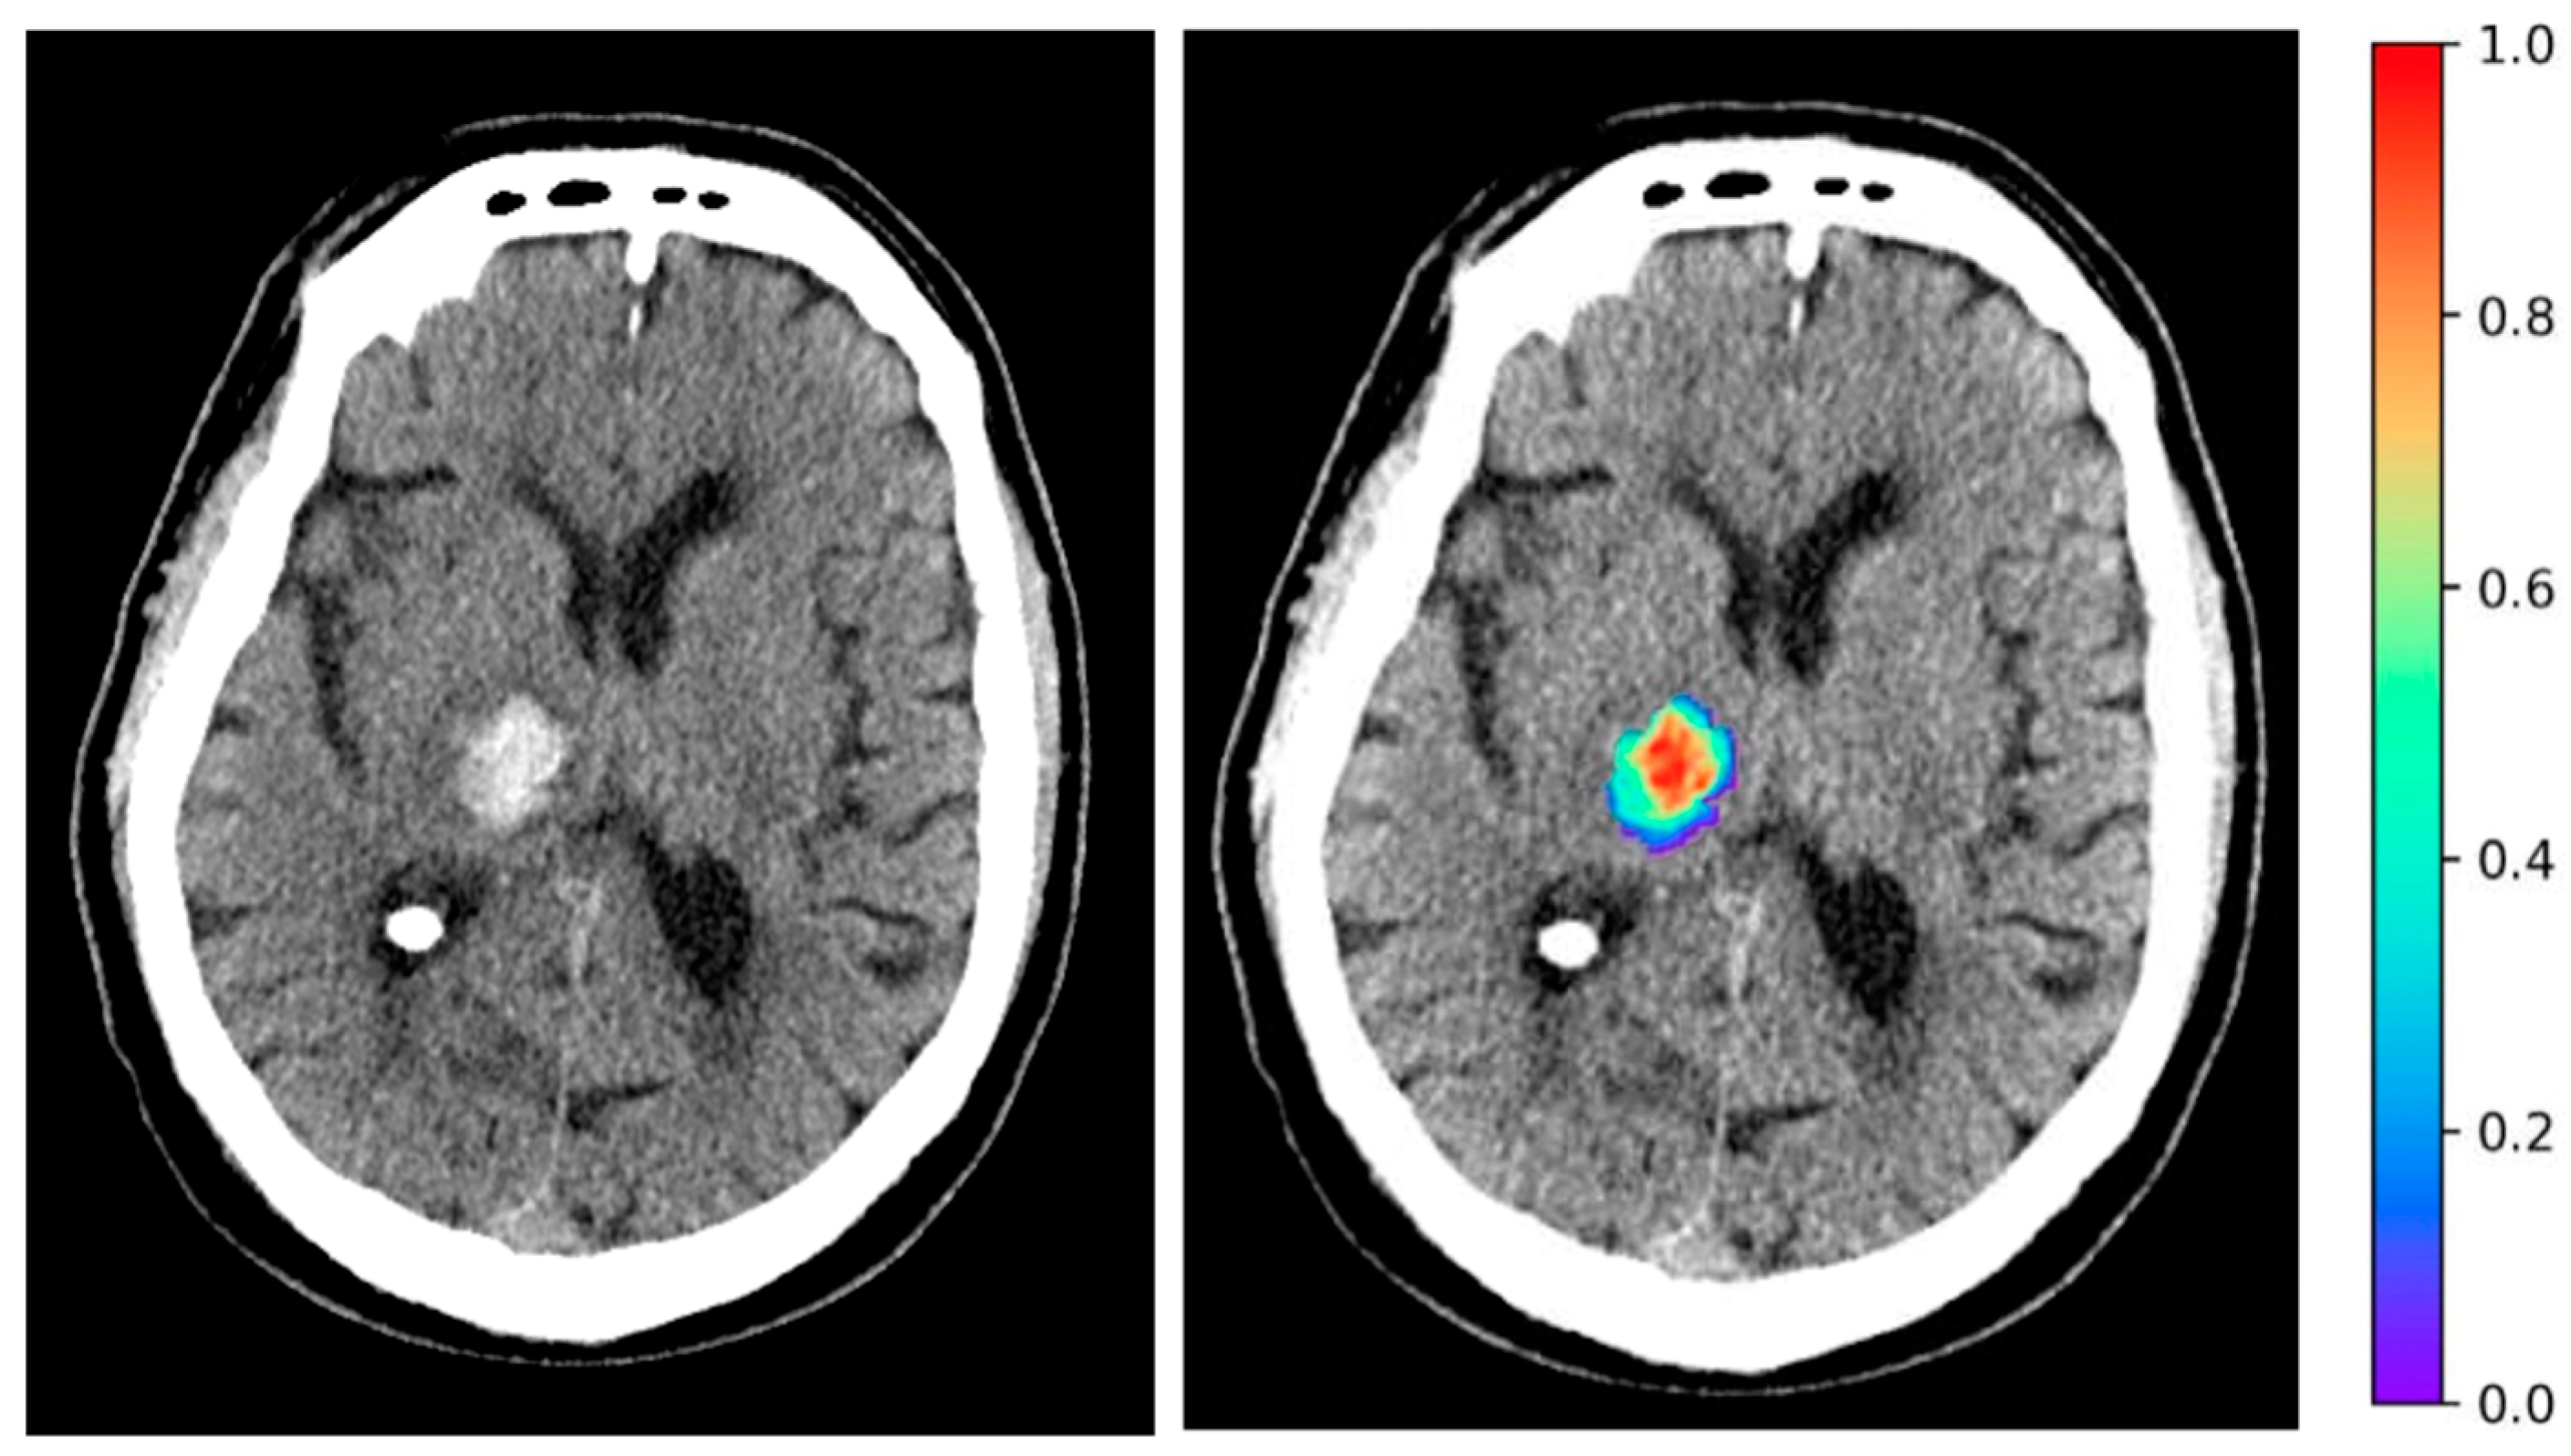

To evaluate the potential associations between clinical variables and ICH radiomic features with survival outcomes, we utilized univariate Cox proportional hazards models in our discovery cohort. Figure 1A depicts the Forest plot of the hazard ratios (HRs) for significant clinical variables. An older age, higher admission NIHSS, and baseline INR were associated with higher probability of death. Conversely, a higher baseline GCS was associated with a reduced likelihood of mortality. The top 20 radiomic features of ICH on admission non-contrast head CTs which are associated with survival, ranked by their HRs, are depicted in Figure 1B. Notably, the original first-order energy, a feature that represents the sum of squared intensities (magnitude) of the voxel values inside the region of interest, was the most significant feature associated with an increased probability of death (HR = 1.64, p < 0.001). Figure 2 is a representative example, color-coding the original first-order energy feature of an ICH lesion on an axial slice of a head CT scan.

4. Discussion

Figure 2. Example highlighting the ICH lesion original first-order energy radiomic feature on an axial slice of head CT scan.